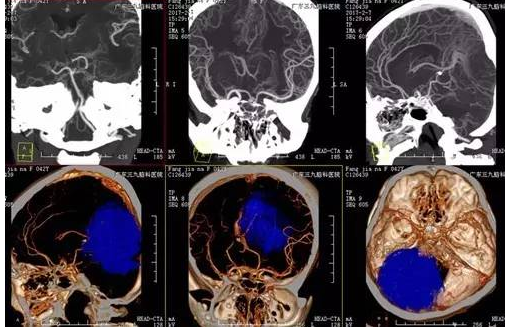

入院后完善相关术前检查, CTA显示肿瘤血供丰富,磁共振增强邻近脑组织稍扩大,显示肿瘤大小8.0cm*7.2cm*6.5cm,考虑到患者瘤体大,血管丰富,为保证病人的安全,科室专家讨论,选择择期全麻下行“小脑幕脑膜瘤切除术”,手术由神经外一科主任张良主刀完成,术程顺利,术后患者恢复良好,未见明确并发症,术后MR提示肿瘤切除,术后病理提示纤维细胞型脑膜瘤(WHO I级)。

术前CTA

术前完善的影像学检查有利于更好地手术评估,制定翔实的手术方案,CTA及MRI为必不可少。本例患者CTA示肿瘤内血管丰富,邻近左侧大脑后动脉受压向右侧移位,MR呈长等T1长等T2异常信号影,增强后病变不均匀明显强化,局部向幕下呈结节状突出,范围约为8.0cm*7.2cm*6.5cm。MRV示:受肿瘤压迫,左侧横窦未见显示,上矢状窦后部变细,直窦显影浅淡;大脑表浅静脉增多。

了解肿瘤的血供及肿瘤与静脉窦之间的关系,在手术入路选择方面有重要意义。手术中除重要神经血管的保护,还应注意直窦、横窦、乙状窦、大脑大静脉等重要血管的保护。肿瘤与静脉窦、脑干、脑神经关系密切,这些都是手术难点。